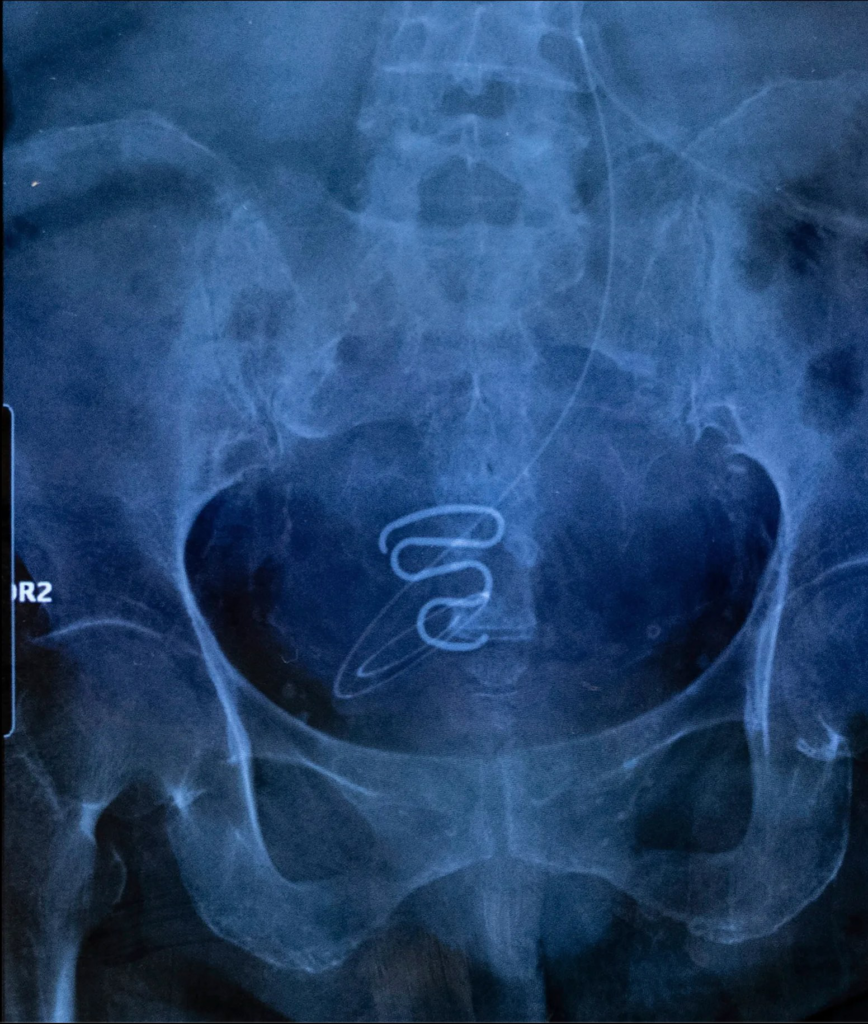

Dieser Preis ging an die Französin Juliette Pavy und ihr Dokumentar-Projekt „Spiralkampagnen“. Hierbei hat sie mit Frauen gearbeitet, die von den Nachwirkungen einer Kampagne der dänischen Regierung in Grönland berichteten: Zwischen 1966 und 1975 wurden etwa 4500 Inuit-Frauen ohne deren Zustimmung Spiralen in die Gebärmutterhöhle eingesetzt. Öffentliche Aufmerksamkeit bekam die Geschichte 2022 durch einen dänischen Podcast. Abgesehen von den vermutlich vielen persönlichen Dramen der Beteiligten in diesem Zusammenhang, handelt es sich aus Mediensicht um eine thematisch perfekte Symbiose aus der Suche nach Gerechtigkeit in Verbindung mit einer Minderheiten-Story, in der zudem Sexualität und weibliche Selbstbehauptung eine wichtige Rolle spielen. Ähnliche Mechanismen, die auf die Bebilderung von Themenwelten mit Wokeness-Perspektive schließen lassen, gelten auch für viele andere der Siegerprojekte: